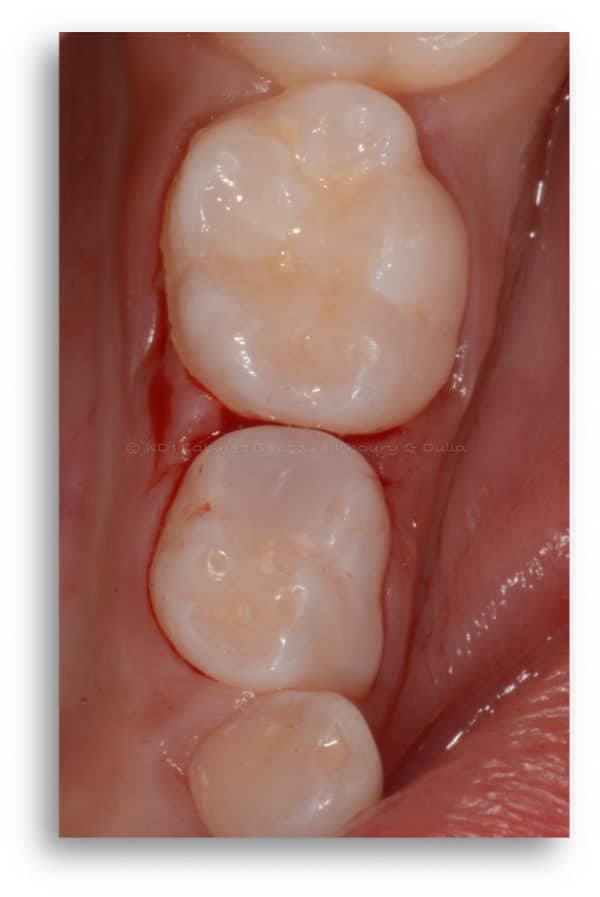

Caries dentaires affectant deux molaires de lait

Caries dentaires affectant deux molaires de lait. Elles peuvent être cachées entre les dents, non détectables lors de l’examen de dépistage. Une petite radiographie intra-orale révélera l’existence de ces caries et évitera leurs progression souvent assez rapide.